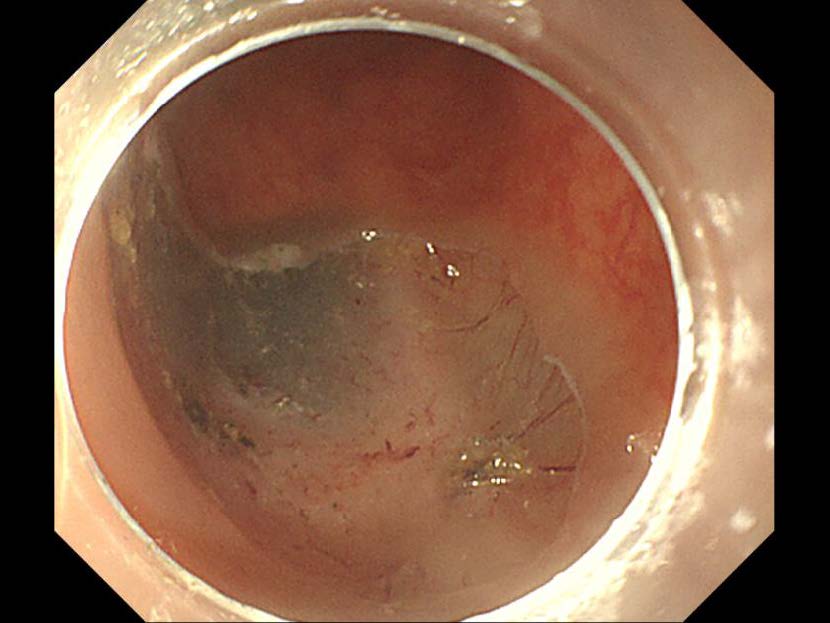

消化管Mapping~大腸~ 2021.10.27

消化器センター 消化器内科

消化管Mapping

消化管Mapping~大腸~

内視鏡検査・治療